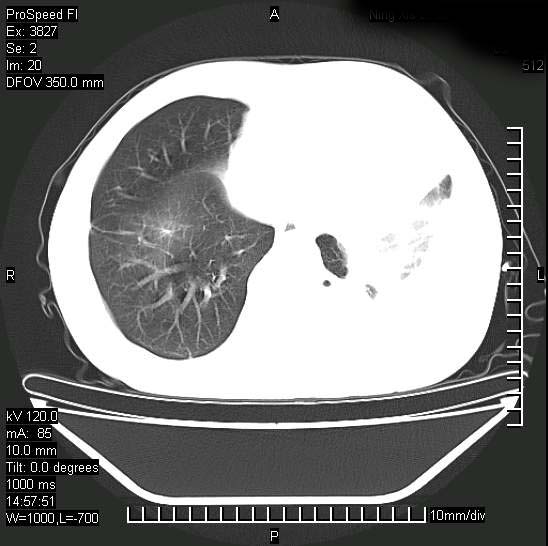

男性,一月前出现右侧肋区疼痛,较剧烈,干咳,无发热,自诉使用抗炎药后缓解,几天前又出现左侧剧烈疼痛,

发热,体温38。9,今天ct,考虑左侧包裹性脓胸,胸腔积液,右上中肺小斑片影,结核/炎症?胸水未见恶性细胞。

左侧肺脓疡,化脓性胸膜炎(脓胸),不支持结核诊断,建议继续抗感染治疗

支持左侧肺脓肿并脓胸,肺内炎症,建议继续抗炎治疗后复查。

脓胸没问题,肺内还可见感染灶,感觉不像是结核性病变.